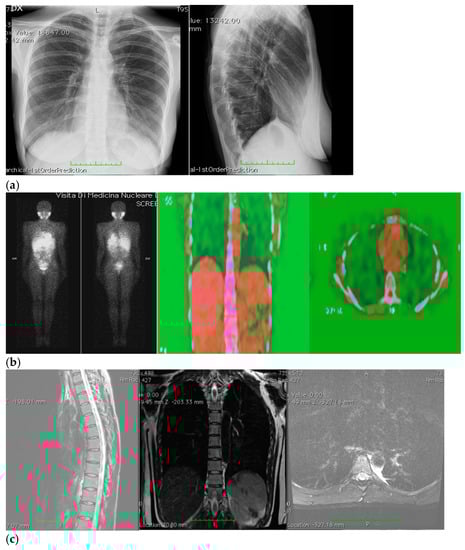

Ten days after surgery, the patient stopped taking her pain medications and was able to sleep on her left side again; afterwards, her sutures were removed, and the patient underwent an imaging check-up, which had negative results (Figure 2).

Figure 2.

(a–c) Imaging assessments for post-surgical evaluation. (a) X-rays. (NOTE: No signs of ongoing pleuropulmonary lesions, free pulmonary bases, each hilum had a normal morphology, heart and aorta within normal limits, normal mediastinum). (b) Total-body scintigraphy with metaiodobenzylguanidine. (NOTE: No longer detectable pathological activity in the left hemithorax. No other areas of significant radiopharmaceutical were observed). (c) Thorax MRI with Gadoteridol. (NOTE: Outcomes of the surgical removal of the well-known left paravertebral lesion and a thin fluid layer corresponding to the surgical cavity. Very little slightly hyperintense remaining tissue in T2-weighted images, with subtle contrast enhancement and a maximum size of about 15 mm, at T6–T6 level, on the left side of the intervertebral foramen, close to the same level costovertebral joint—in a clinical picture which required MRI monitoring with contrast medium overtime).